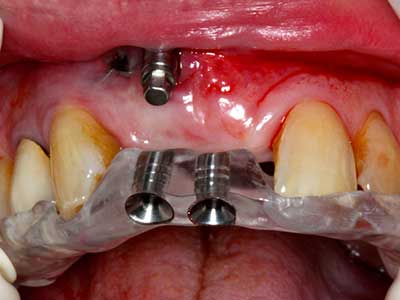

En la extracción de bloques óseos la piezocirugía también presenta ventajas adicionales: Además de la alta precisión en la osteotomía que ya se ha descrito antes, se ha comprobado que el uso de los delgados insertos de sierra resulta especialmente cuidadosas con el hueso. Frente a esto, sobre todo cuando se usan las fresas de Lindemann, cabe esperar pérdidas en la extracción significativamente más altas debido al mayor grosor de la parte frontal del cabezal (Lakshmiganthan, Gokulanathan et al. 2012). La separación basal que se necesita en particular en los injertos de bloque extraídos de forma retromolar se ve facilitada mediante sierras perpendiculares especialmente previstas a tal fin, lo que permite considerar que la cirugía piezoeléctrica es un procedimiento preciso y seguro para la obtención de bloques de hueso en el área retromolar (Happe 2007) (fig. 1-12).

Fig. 1: Preparación de una tapa ósea conforme con Piezomed (W&H, Salzburgo, Austria)

Fig. 2: Defecto del maxilar superior lateral vertical y horizontal con línea de la sonrisa alta, con indicación para la reconstrucción antes del implante.

Fig. 3: La separación basal del bloque se ve facilitada con piezas dotadas de una angulación especial.

Fig. 4: Con la rasqueta ósea se obtienen virutas adicionales de hueso autógeno.

Fig. 5: Comprobación de las dimensiones del bloque en la zona de recepción.